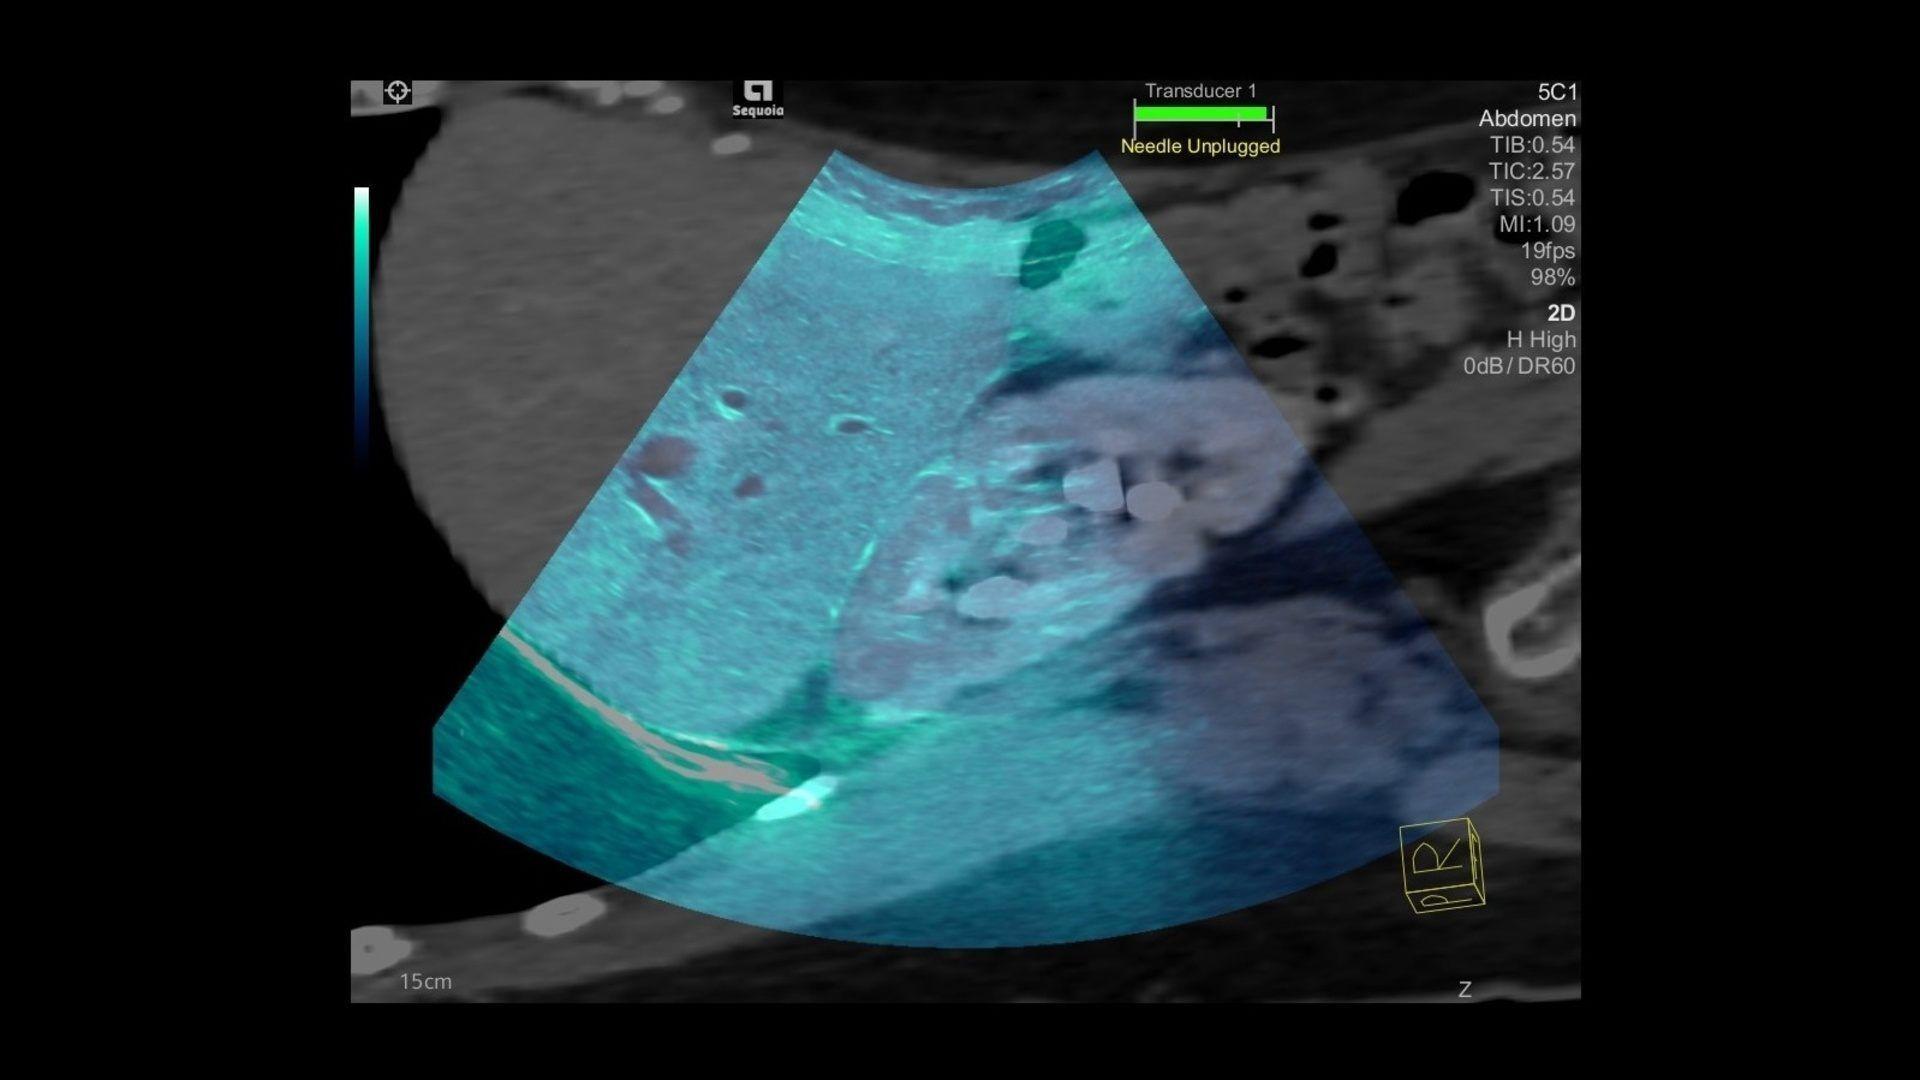

Ultrasound Wallpapers - Top Free Ultrasound Backgrounds - WallpaperAccess

wallpaperaccess.comultrasound sequoia acuson healthineers siemens wallpaperaccess

wallpaperaccess.comultrasound sequoia acuson healthineers siemens wallpaperaccess